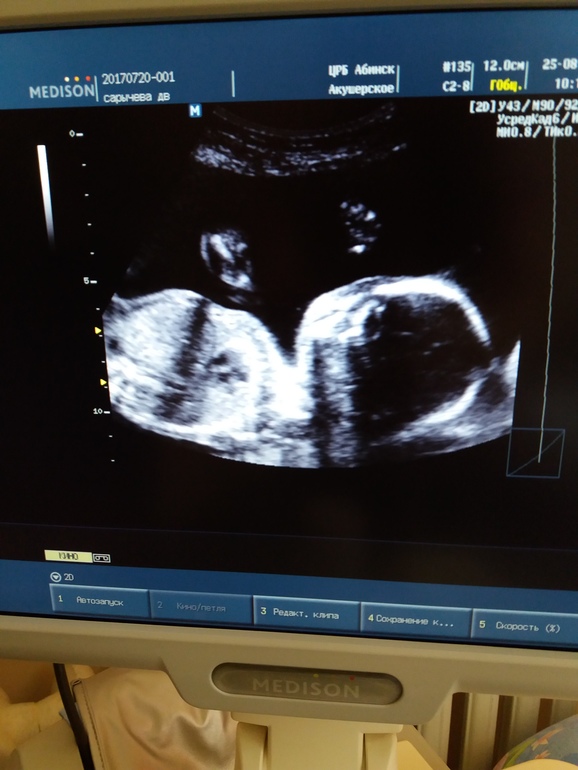

Я тоже не вижу кто в Вашем "домике" живет...сама такая...одних пацанов нарожала, а так и не научилась по УЗИ определять пол малыша. В предпоследнюю беременность, на сроке 22 недели, врач на мониторе мне показала конкретный такой "огуречик с помидорками"...ну, точнее "корнишон с черри"))) А в крайнюю беременность только на сроке 31 неделя узнали, что снова богатырь...до этого никому ничего не показывал, хитрец!